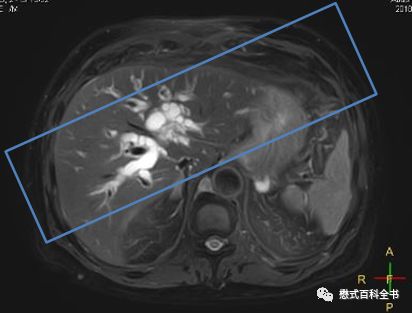

图19:MRCP扫描角度二

如上图所示,第二种扫描角度,是在3D冠状位扫描的时候,在横轴位上,扫描角度平行于左、右肝内胆管走形。使用该定位角度显示左、右肝内胆管及肝总管比较好,而且大家注意,使用这种角度,配合合适的FOV和扫描层数可以躲避到腹主动脉。而使用第一种定位角度,一般是无法躲避腹主动脉的。